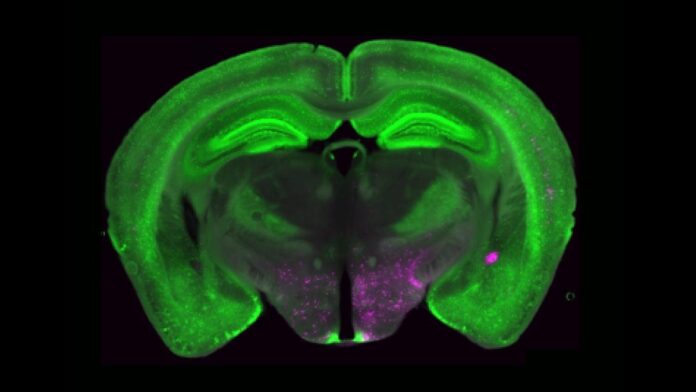

In a new study, Betley and researchers from the University of Pittsburgh and Scripps Research Institute identified a set of brain cells that play a central role in controlling chronic pain. These cells, known as Y1 receptor (Y1R)-expressing neurons, are found in a part of the brainstem called the lateral parabrachial nucleus (lPBN). They become active in long-lasting pain states but also process other signals tied to hunger, fear, and thirst. This overlap suggests that the brain can adjust pain responses when other survival needs are more pressing.

The researchers also characterized the molecular and anatomical identity of the Y1R neurons in the lPBN. They found that Y1Rneurons didn’t form two tidy anatomical or molecular populations. Instead, these neurons were scattered across many other cell types.

“It’s like looking at cars in a parking lot,” Betley says. “We expected all the Y1R neurons to be a cluster of yellow cars parked together, but here the Y1R neurons are like yellow paint distributed across red cars, blue cars, and green cars. We don’t know exactly why, but we think this mosaic distribution may allow the brain to dampen different kinds of painful inputs across multiple circuits.”